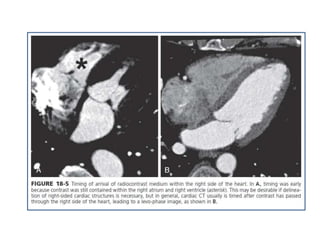

• Timing of the scan in relationship to the contrast bolus is

commonly performed using the triggered bolus method, in

which contrast attenuation in the pulmonary artery or aorta is

monitored, followed by automated scan initiation once an

adequate CT attenuation value (110 to 180 Hounsfield units

[HU]) is achieved.